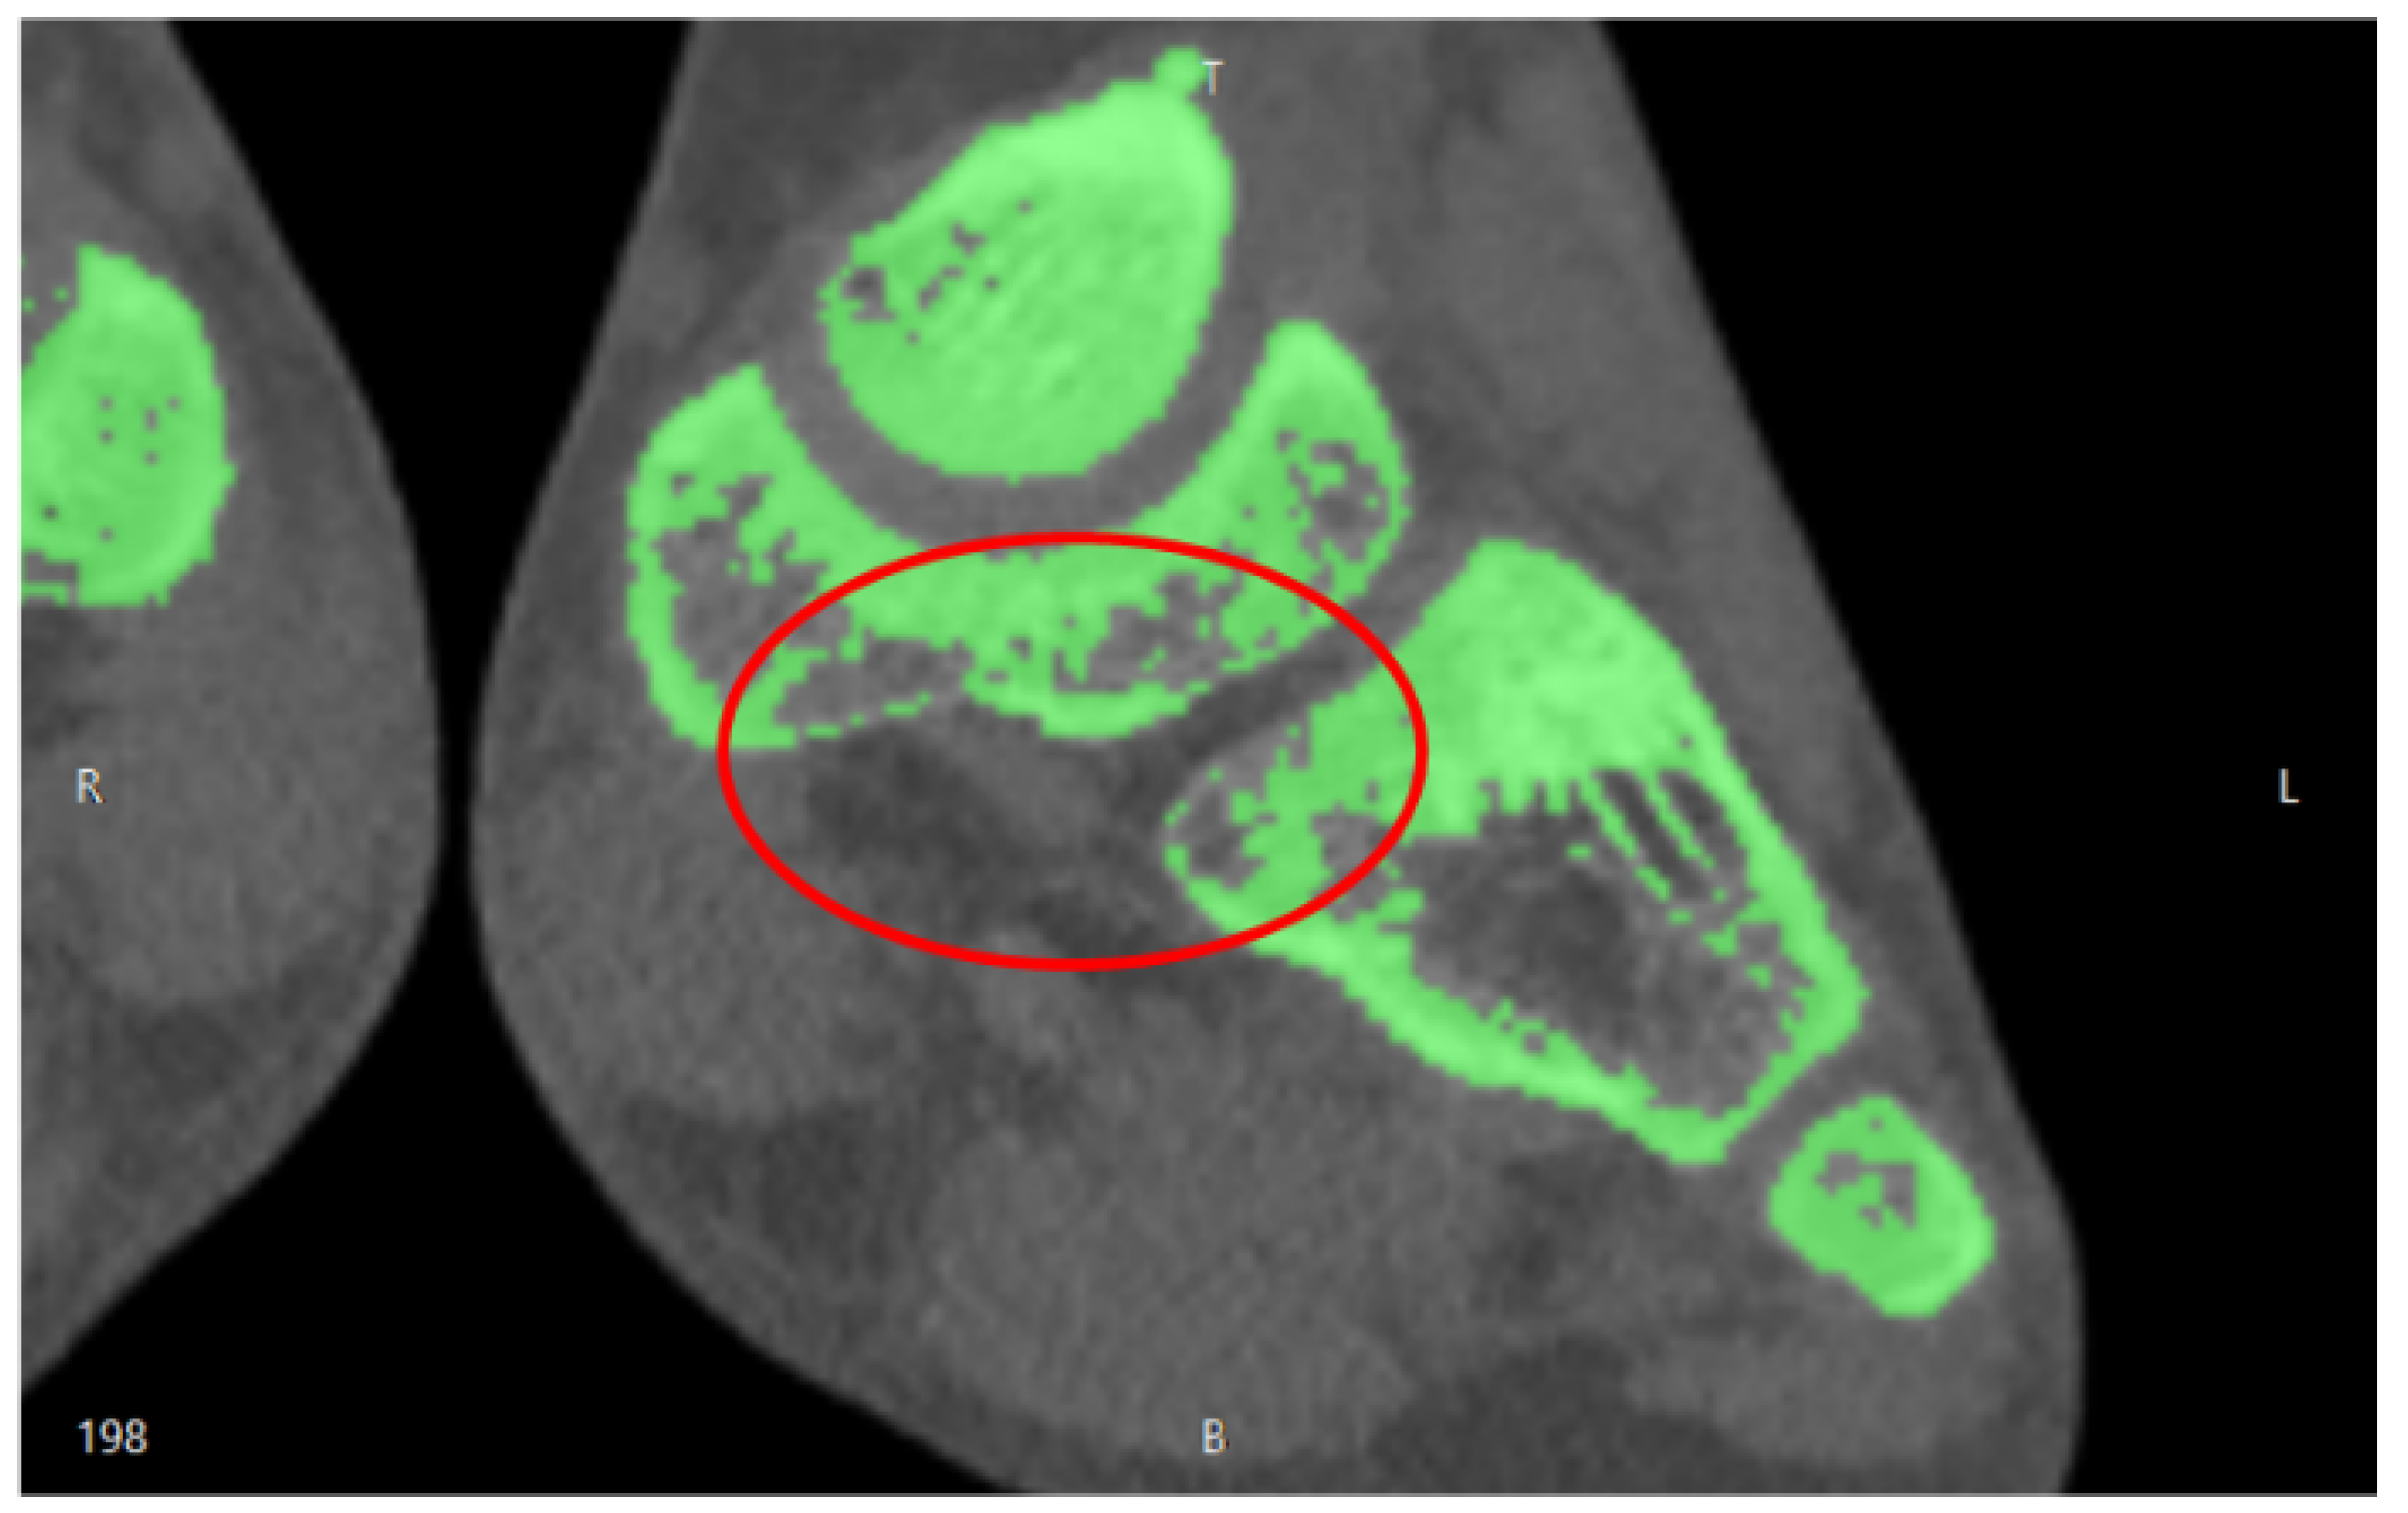

3.1. Imaging Acquisition and Mesh Processing